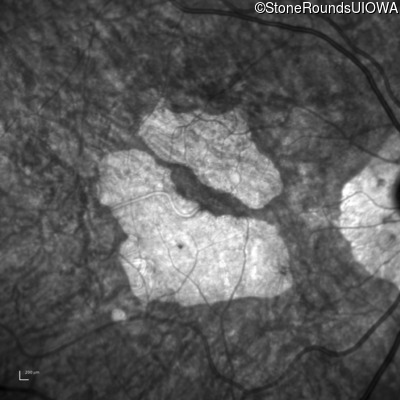

AR Stargardt Disease (IIA)

Age at visit: 69 years

This 69 year old man had excellent vision until 7 years ago when he first noticed some difficulty in dim light especially while driving.

AR Stargardt Disease ABCA4 Trp1101Stop TGG>TAG IVS30+1321 A>G AR